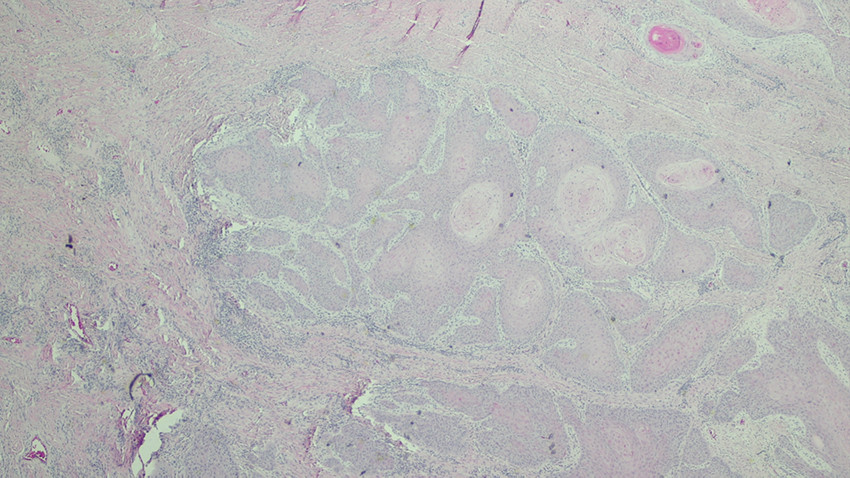

Verrukøst karsinom kan oppstå ved kronisk inflammasjon plantart mange år etter skade (2). Uavhengig av lokalisasjon er verrukøse karsinomer alltid plateepitelkarsinomer. Slike lesjoner kjennetegnes av eksoendofytisk vekst, der den endofytiske komponenten viser minimal eller ingen sikker cytologisk atypi. Disse karsinomene er dermed usedvanlig høyt differensiert, og ikke mulig å skille fra reaktiv prosess i tidlig fase eller i en overfladisk biopsi. Ved karsinomutvikling er en avhengig av tilstrekkelig dyp biopsi, der en får fremstilt tumors relasjon til dypere deler av underliggende stroma for å stille diagnosen med sikkerhet (3, 4).

Pasienten samtykket til en leggamputasjon, som ble gjennomført med 15 cm bevart tibia 20 cm fra proksimale sårkant med en bakre lapp til lukking av stumpen. Histologi av amputatet bekreftet et høyt differensiert plateepitelkarsinom svarende til et verrukøst karsinom, med dybdevekst på minst 10 mm, men uten påvist infiltrasjon i fettvev, perinevralt eller i fascie/muskulatur (Figur 5). Diagnosen plateepitelkarsinom ble stilt med antatt stadium T3 N0 M0 (AJCC-8) (5).